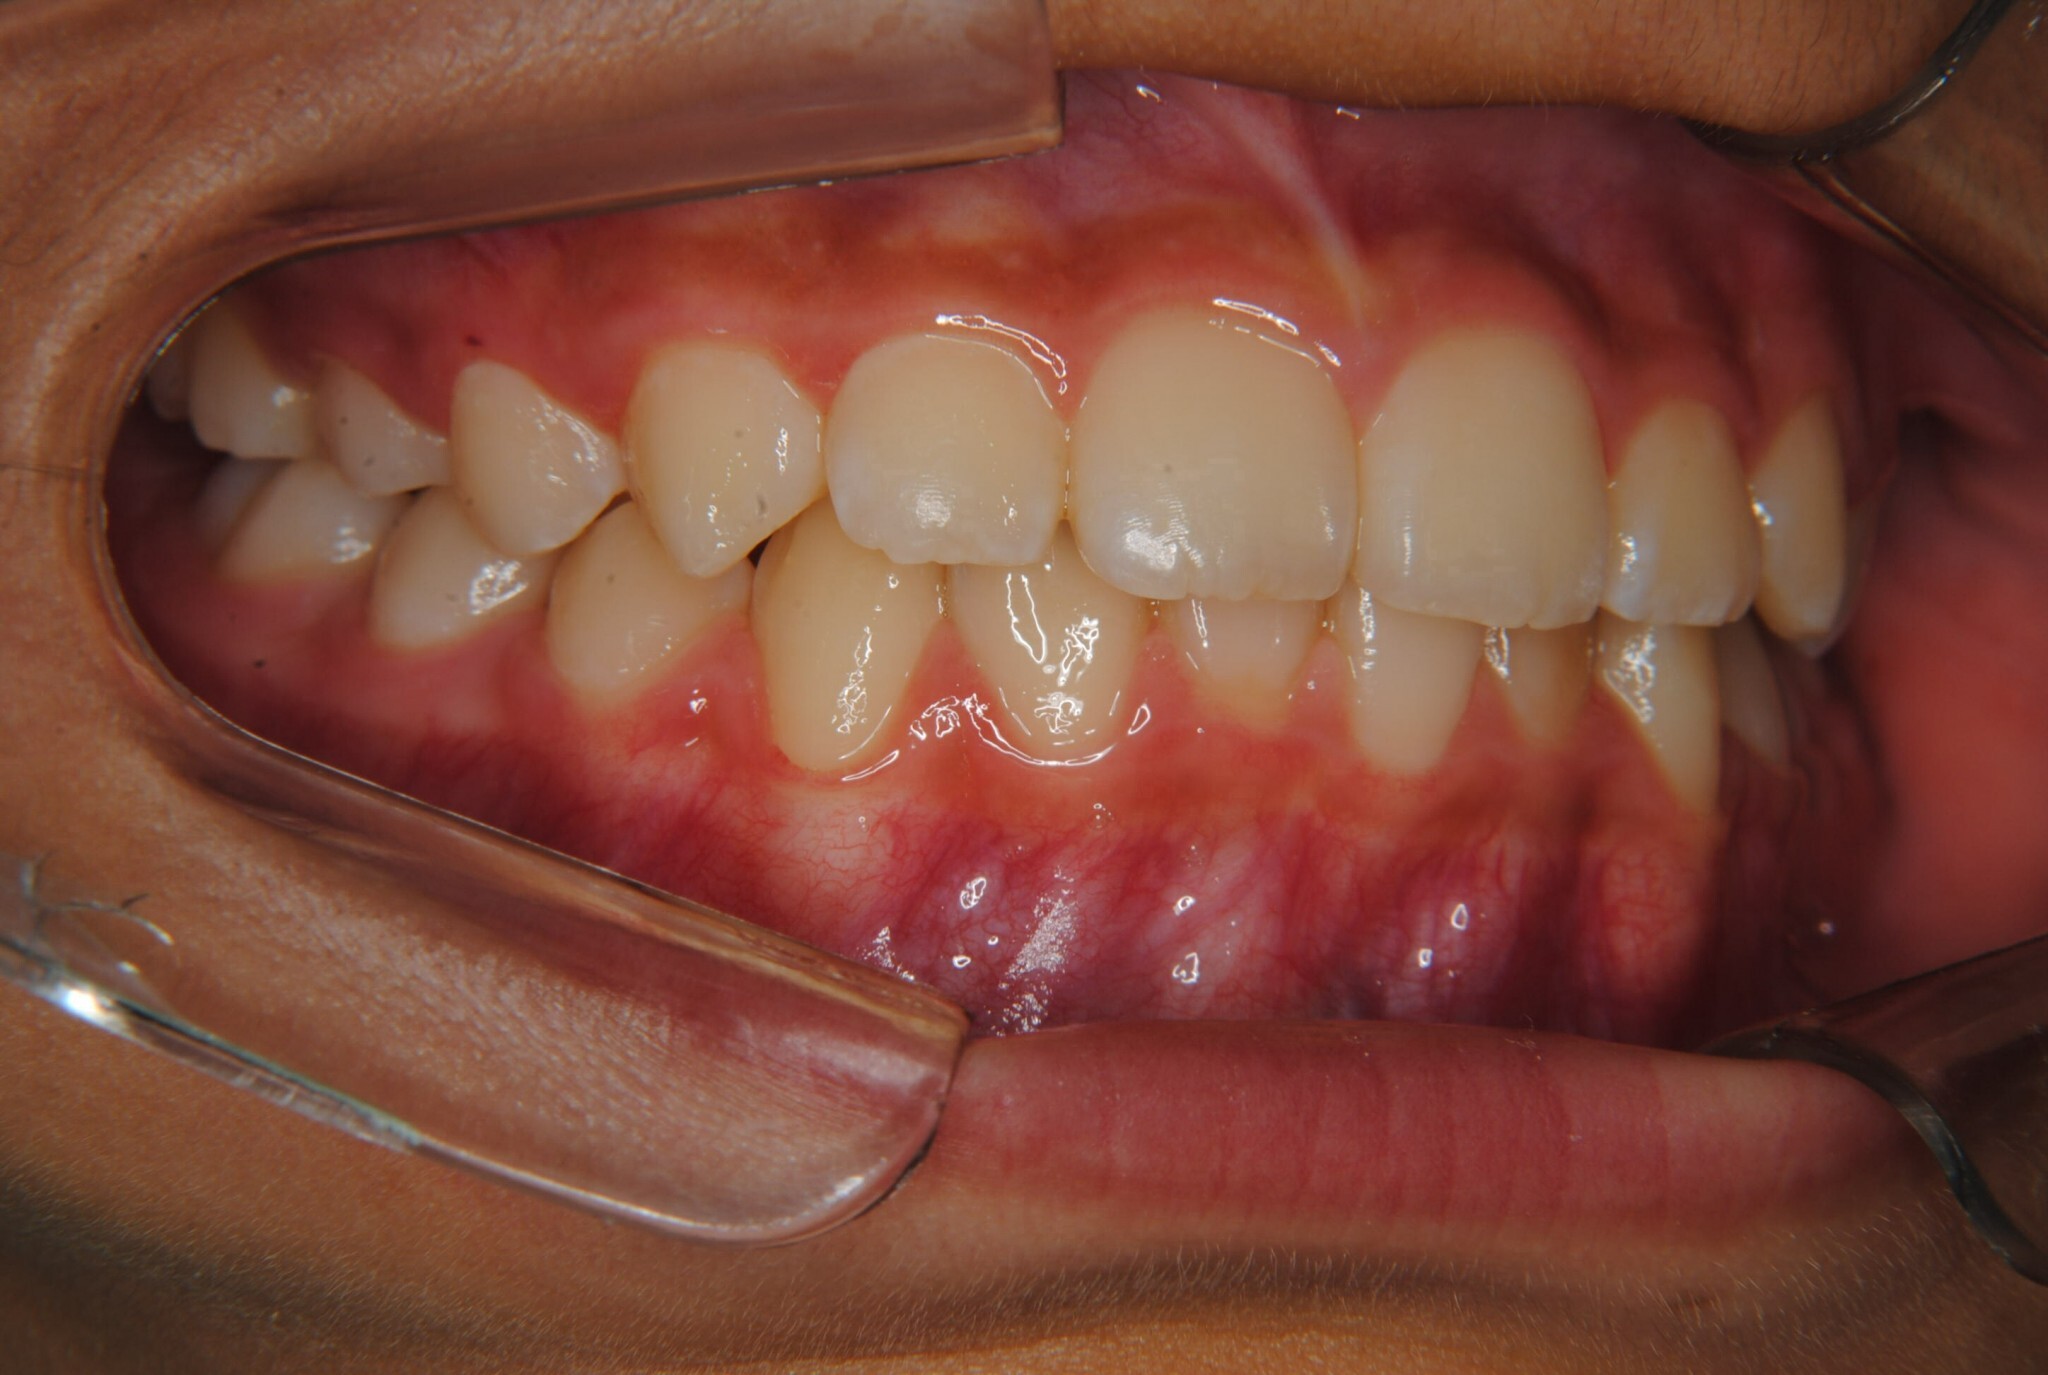

②診断名:Ⅰ級叢生

③年齢:初診時(左写真)8歳6か月、終了時(右写真)11歳4か月

⑧リスクと副作用:特に大きなリスクや副作用はありませんでした。拡大床装着直後は違和感があったようですが、特に痛みを感じることなく6.5mmまで拡大できました。その後永久歯への生え変わりも順調で、ほぼ正常な咬み合わせになりました。この後11歳4か月まで観察し、7番目の奥歯である12歳臼歯がきちんと咬んだので終了となりました。